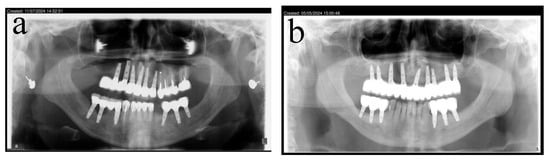

2.3. Illustration Case (Patient No. 21)

A 42-year-old female patient was referred to our clinic for bilateral augmentation of the posterior mandible and dental implant placement. The patient was in good health, presenting with bilateral posterior mandibular edentulism (Kennedy Class I) (Figure 1a,b). The CBCT scan revealed severe horizontal atrophy of both posterior mandibular ridges, with knife-edge residual ridges (Figure 1c,d). Narrow implants or ridge splitting were not viable options. Therefore, bone augmentation was required to achieve the treatment goal. The patient was treated using the honeycomb technique.

(a) Bilateral posterior mandibular edentulism. (b–d) Computed tomography showing severe horizontal atrophy with knife-edge residual ridges.